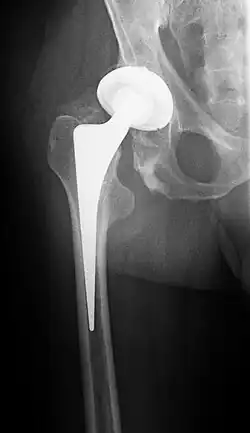

Hüft-Totalendoprothese

Häufig erfolgt die Versorgung der medialen Schenkelhalsfraktur beim alten Menschen durch Implantation einer Hüfttotalendoprothese oder Hemiprothese (Duokopfprothese).[10][11] Begründet wird dieses Vorgehen mit dem hohen Risiko einer späteren Femurkopfnekrose. Eine Zweitoperation aus diesem Grund soll dem älteren Patienten nach Möglichkeit erspart werden. Des Weiteren dürfen Patienten nach einer Totalendoprothese oder Duokopfprothese wesentlich schneller wieder die betroffene Seite belasten, was das Risiko einer drohenden Immobilität der vorwiegend älteren Patienten erheblich senkt.

Hüftgelenk-Endoprothesen (sowohl Hemi- als auch Totalendoprothesen) wurden seit Beginn ihrer Entwicklung nicht nur zur Behandlung der Coxarthrose, sondern auch zur definitiven, primär belastungsstabilen Behandlung der medialen Schenkelhalsfrakturen vor allem älterer Menschen eingesetzt.